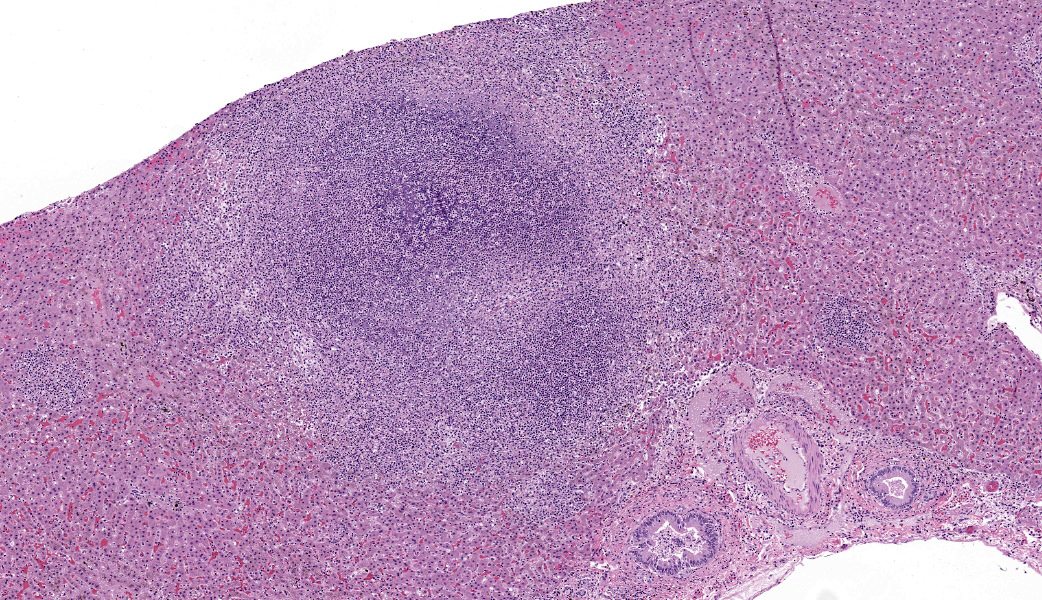

Liver: Approximately 40% of the hepatic lobular architecture is effaced by multifocal periportal to random discrete foci of lytic necrosis. Foci are composed of cellular debris, fibrin, myriad intact and fragmented neutrophils and moderate numbers of macrophages. There are small numbers of macrophages with tan to brown cytoplasmic pigment (hemosiderin vs. lipofuscin). Portal triads contain up to four biliary duct profiles (biliary hyperplasia) and are surrounded by moderate numbers of lymphocytes, plasma cells, and macrophages. Moderate numbers of scattered hepatocytes contain brown granular cytoplasmic pigment (lipofuscin vs. hemosiderin) and cytoplasmic large discrete vacuoles. Multifocally, small hepatic vessels are partially occluded by aggregates of eosinophilic homogenous material interspersed with pyknotic debris, fragmented neutrophils, and macrophages (fibrin thrombi). Hepatic sinusoids are variably expanded with moderate numbers of erythrocytes (congestion), similar inflammatory infiltrates, and fibrin thrombi.Spleen: Approximately 20% of the splenic parenchyma is effaced by multifocal to coalescing foci of necrosis and inflammation (similar to those described in the liver). Multifocally, the center of lymphoid follicles is hypocellular with eosinophilic karyorrhectic debris, extracellular yellow brown pigment globules (hematoidin), and moderate numbers of macrophages containing yellow brown cytoplasmic pigment (suspect hemosiderin). Splenic vessels are multifocally partially occluded by fibrin thrombi.

- Liver: Moderate subacute multifocal random necrosuppurative hepatitis with periportal lymphoplasmacytic and histiocytic cholangiohepatitis and mild biliary hyperplasia

- Spleen: Moderate subacute multifocal necrosuppurative splenitis with lymphoid necrosis

- Liver: Hepatitis, necrosuppurative, acute, multifocal, moderate, with fibrin thrombi.

- Spleen: Splenitis, necrosuppurative, acute, multifocal, moderate, with fibrin thrombi.